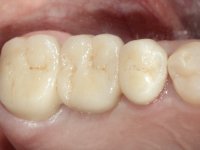

Teeth 17 and 16 were prepared for the fabrication of a 2-element Zr bridge. The impression was performed with a double mixing technique and a monolithic bridge in Zr was made in the laboratory. 4 years later, an abscess appeared in the apical area of tooth 26. It was decided to remove the bridge, remove the intra-radicular posts and retract the endodontic treatments of teeth 17 and 16. The removal of the bridge was carried out by making two cervical cavities. in the palatal area of the bridge and with a microluxator, disinsertion movements were performed. The intra-radicular posts were removed using fine drills and an ultrasound tip. The bridge was provisionally cemented and the patient was referred to a fellow endodontist for endodontic retreatment. After the retreatment, the intraradicular posts were placed again and the bridge was definitively cemented. One year later, a new abscess appears, possibly related to a root fracture. The bridge was sectioned between tooth 27 and 26 and tooth 26 was extracted and the crown of 27 was provisionally cemented. 3 months later, teeth 27 and 25 were prepared and a temporary bridge was made in dual polymerization resin. Then, an impression was made using the double mixing technique and a 3-element bridge in Zr was made in the laboratory. It was permanently cemented in the mouth with resin-reinforced glass ionomer cement.